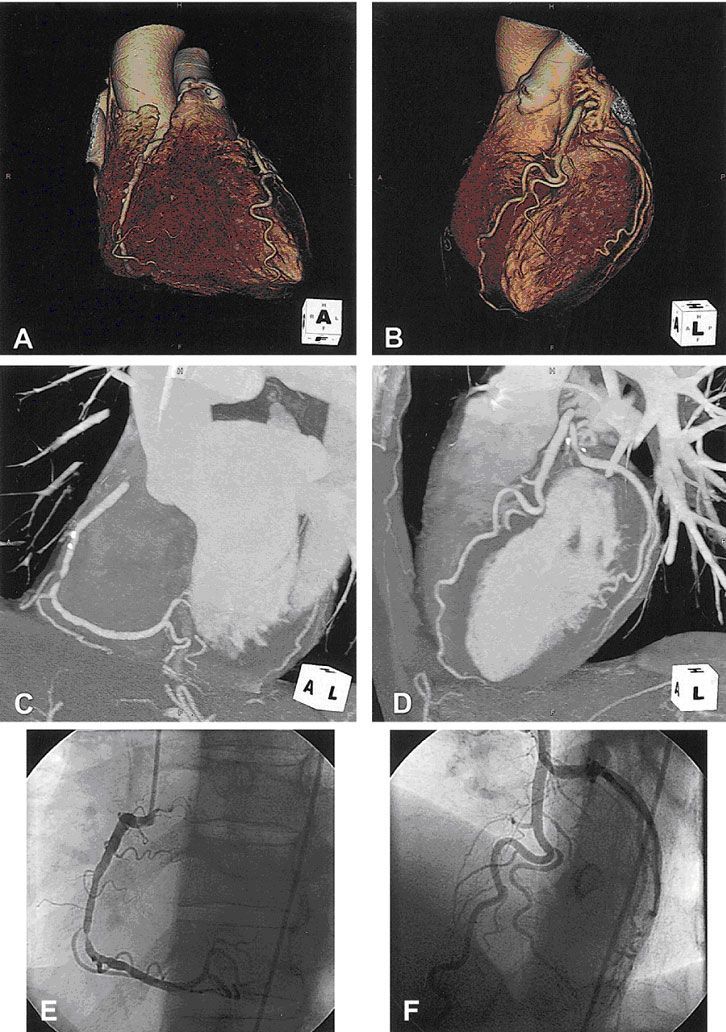

С помощью МСКТ описана возможность визуализации бикуспидального аортального клапана (рис № 20,21), выявление вегетаций на аортальном клапане при инфекционном эндокардите [43] (рис № 24).

![]() |

| Рис.18-19. МСКТ. Артальный клапан (слева), митральный и аортальный клапаны (справа). Норма. |

Известно, что пациенты с бикуспидальным аортальным клапаном имеют высокий риск развития аневризмы восходящего отдела аорты и ее диссекции, поэтому у таких пациентов важна точная диагностика поражения, для проведения своевременной хирургической коррекции данной патологии.

| Рис.20-21. Слева - бикуспидальный аортальный клапан (стрелка). Справа-кальцинированный бикуспидальный аортальный клапан (стрелка). |

| Рис.22-23. Кальциноз аортального клапана (стрелка). Справа протез аортального клапана. |